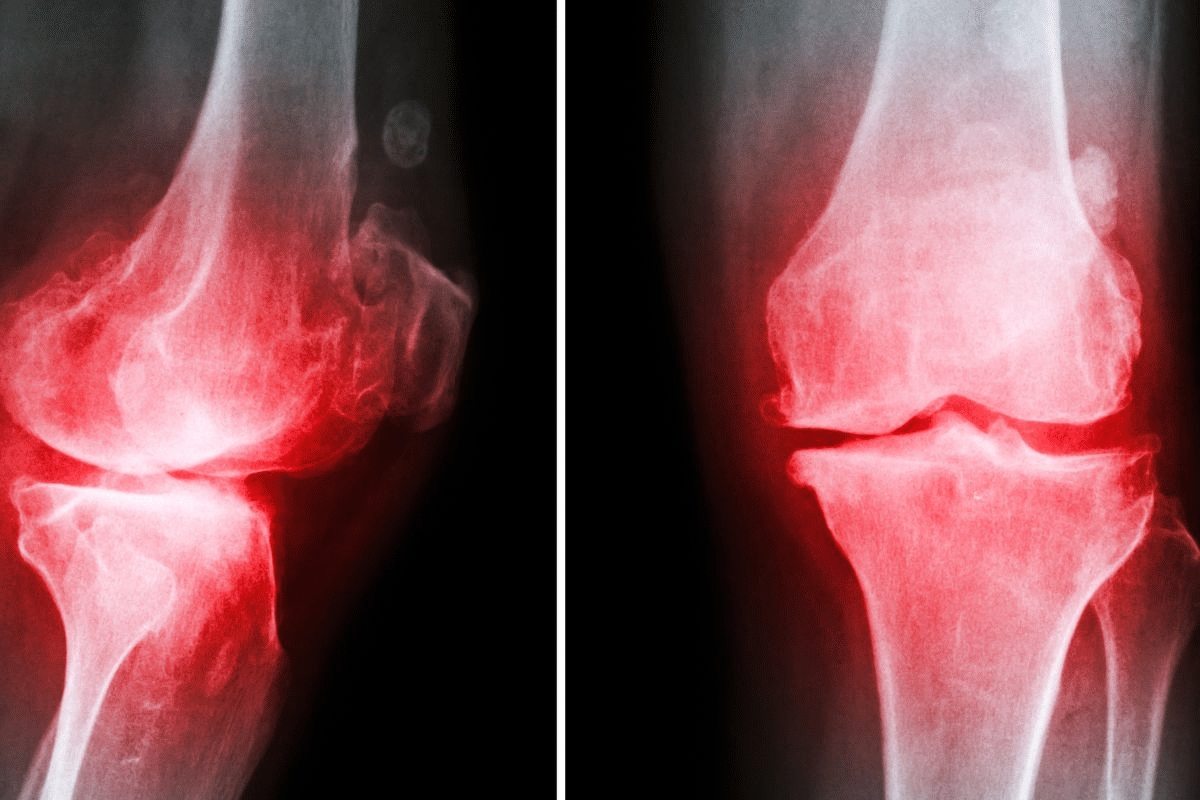

It’s important to know about the different types of inflammatory joint diseases. These conditions can really hurt your quality of life. They cause pain, stiffness, and make it hard to move.

Rheumatoid arthritis (RA) is a chronic condition that mainly affects the joints. It causes inflammation, pain, and can damage the joints over time. If one hand is affected, the other hand usually is too.

Osteoarthritis (OA) is the most common arthritis. It’s often called “wear and tear” arthritis. It happens when cartilage in joints breaks down, causing pain. Unlike RA, OA is not an autoimmune disease but a degenerative condition.